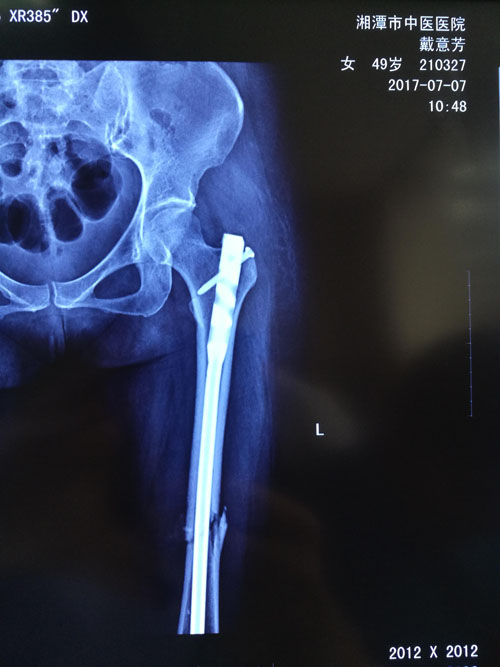

典型病例:閉合復(fù)位髓內(nèi)釘治療股骨骨折,創(chuàng)傷小、出血少,骨折愈合快。